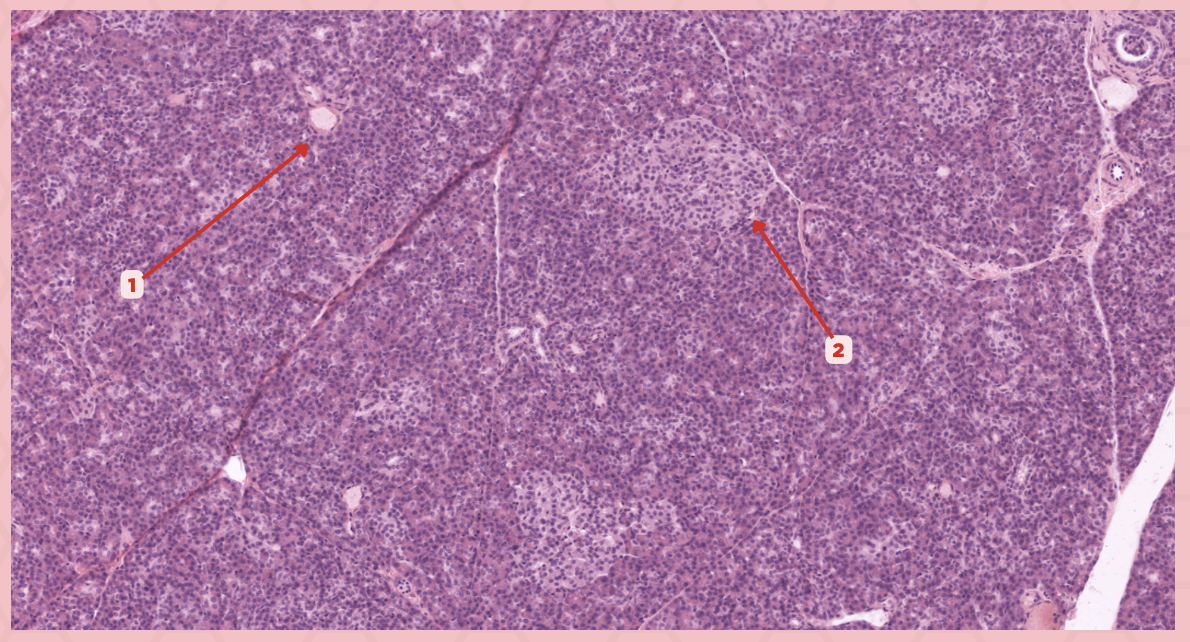

Islets of Langerhans

Identify the structure labeled as 1.

Pancreatic Acini

Identify the structure labeled as 2.

Reticular Tissue

Identify the structure labeled as 3.

Beta-cells

Which cells occupy the central area of #1?

Pancreatic Acini

#3 delineates the pale- staining cells from the darker-staining cells. What do you call the darker-staining cells?